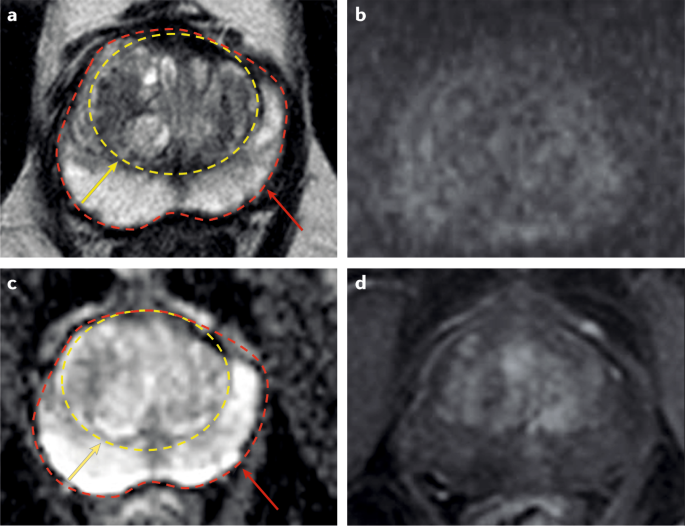

what is the first line investigation for prostate cancer and how are the results reported?

A

Multiparametric MRI of the prostate

reported on a Likert scale, scored as:

• 1 – very low suspicion

• 2 – low suspicion

• 3 – equivocal

• 4 – probable cancer

• 5 – definite cancer

radiologist can predict likelihood of cancer from this